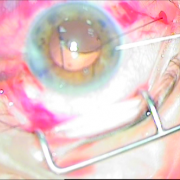

Διαθέτουμε την εμπειρία για χρήση ειδικών τύπων ενδοφακών, όπως είναι οι αστιγματικοί οι πολυεστιακοί, οι ιριδικής στήριξης και πολλών άλλων. Όλα αυτά συμβάλλουν στην αντιμετώπιση του καταρράκτη με ποιοτικό και εξατομικευμένο τρόπο.

ιριδικής στήριξης